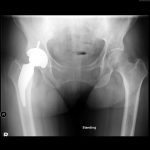

Pre-Op AP Pelvis

Harris Hip Score 31 (max=100) | Oxford Hip Score 9 (max=48)